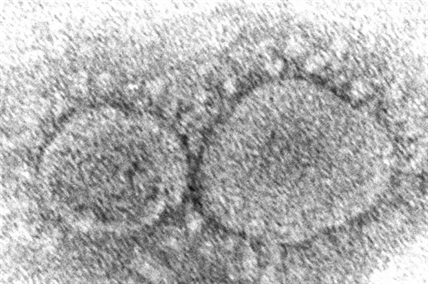

841 new COVID-19 cases in B.C.; 74 in Interior Health

B.C. health officials reported 841 new cases of COVID-19 today, 74 of which were in…

No new COVID-19 deaths in B.C.; 799 new cases

B.C. health officials are reporting 799 new cases of COVID-19 since yesterday, with 96 in…

COVID-19 modelling shows B.C. bending the curve of variant cases

VANCOUVER – Efforts by British Columbia health officials and residents are managing to suppress infections…